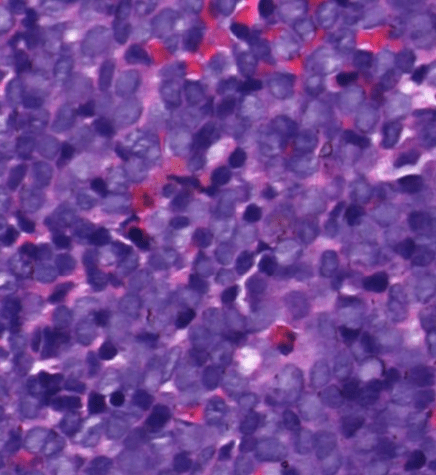

Pathology Lab 1

應該會考